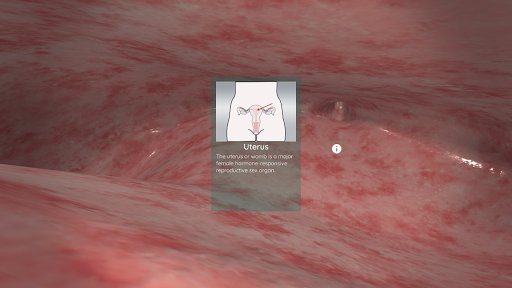

En utilisant la réalité virtuelle, vous serez capable de naviguer le long des structures anatomiques, devenant une partie de l'anatomie humaine: circulatoire, respiratoire, digestive, urinaire, lacrymale et système reproducteur féminin.

En mode Réalité virtuelle, un appareil mobile (smartphone) doit être inséré dans un gadget de réalité virtuelle pour profiter d'une expérience totalement immersive. L'utilisateur peut interagir avec les commandes de navigation et les éléments d'information anatomiques en les visant.

Bien qu'il offre la meilleure expérience lorsqu'il est utilisé en mode réalité virtuelle, l'utilisateur peut également profiter et apprendre avec cette application mobile en mode plein écran, sans les besoins d'un gadget de réalité virtuelle.